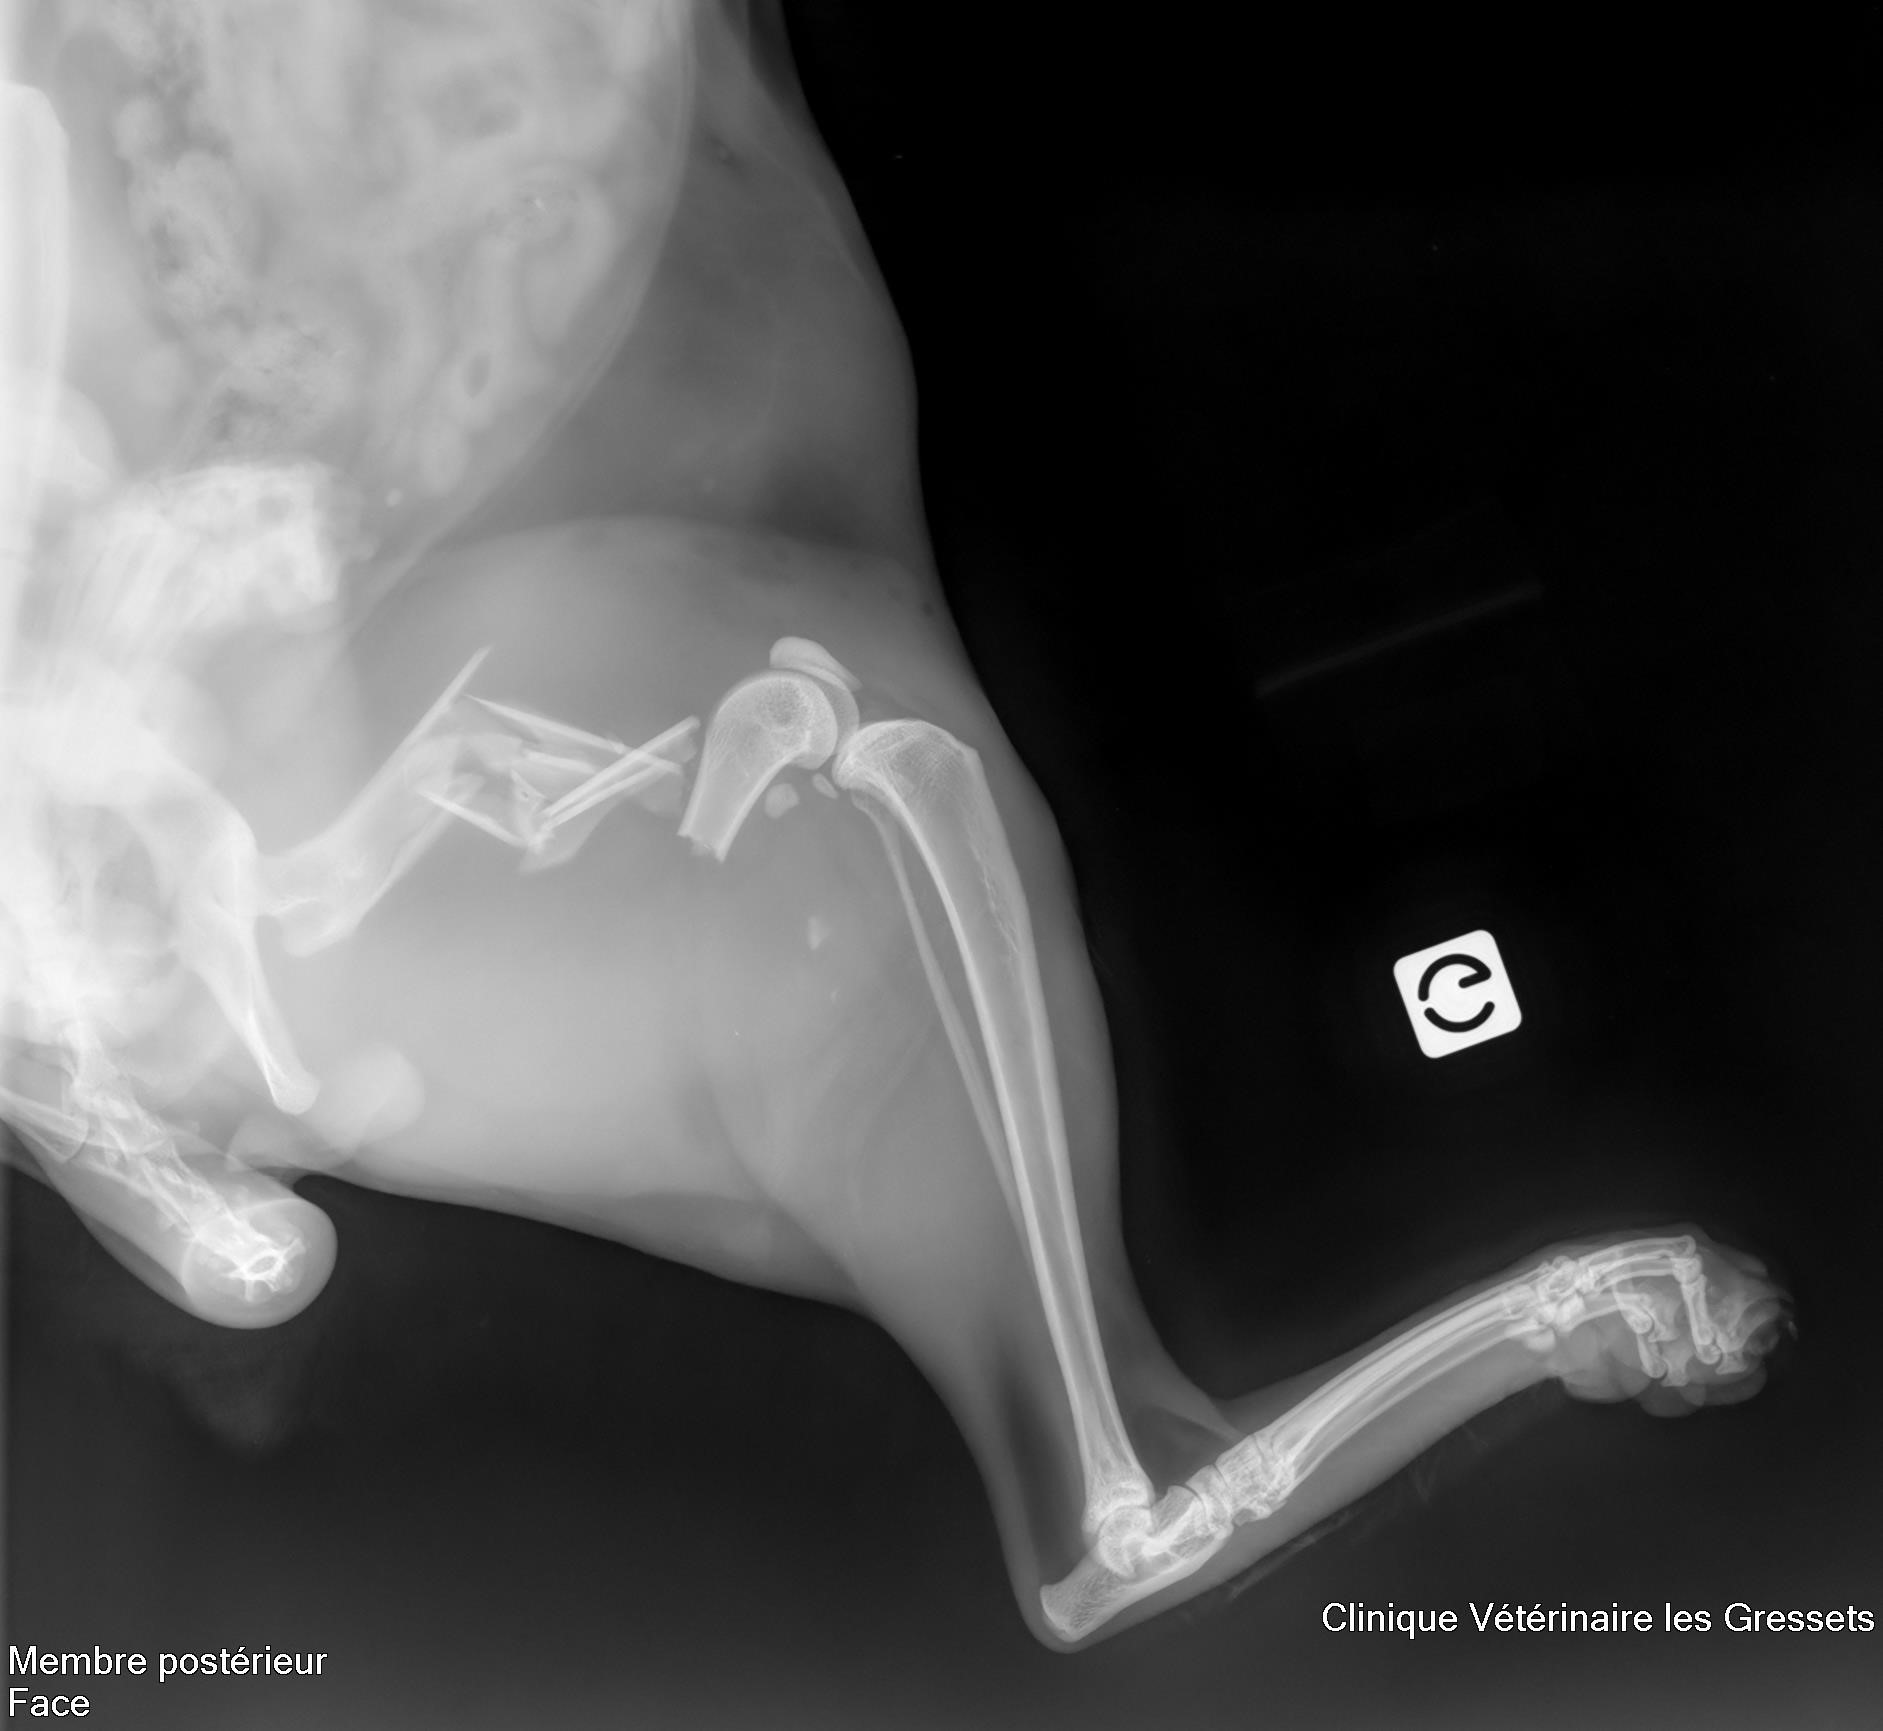

Voici Thor, notre rescapé qui est tombé de 7 étages 🙀 !!! Thor a eu beaucoup de chance malgré son accident, une chute de cette hauteur est malheureusement souvent fatale… Il a eu de multiples fractures en plus de saignements importants et de lésions internes. On vous montre une de ses radios 🩻, pour que vous vous rendiez compte des dégâts !